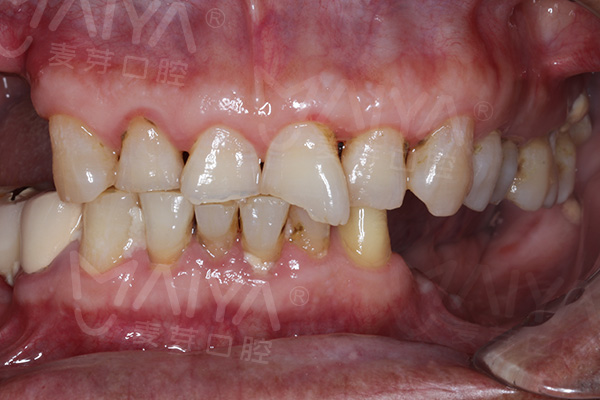

陈老伯种牙前口内照